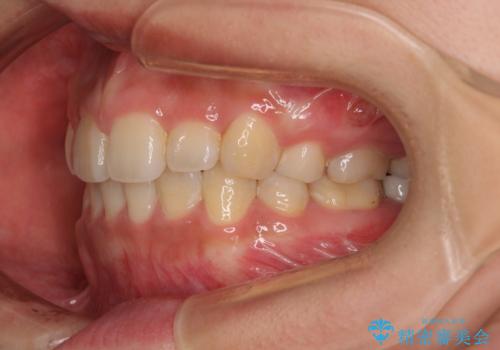

デコボコと膨らんだ口元 ハーフリンガルによる抜歯矯正とインプラント補綴治療

- 前歯のデコボコと上顎の前突感による口の閉じにくさを気にして来院された患者様です。

デコボコの解消までは非常にスムーズでしたが、咬合力が強いためか、スペースを閉じるまでに長い期間を要しました。

矯正治療途中にインプラント埋入と仮歯の装着を行ったことで、しっかりとした奥歯の咬み合わせで終了させることができました。